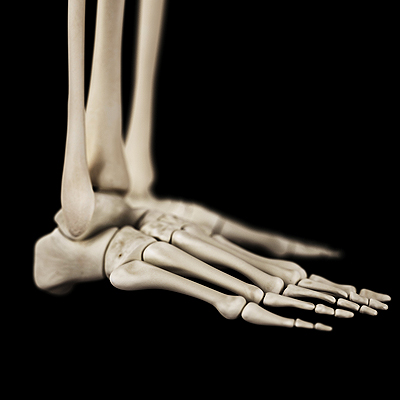

Dealing with Stress Fractures of the Foot and Ankle

Stress fractures occur in the foot and ankle when muscles in these areas weaken from too much or too little use. The feet and ankles then lose support when walking or running from the impact of the ground. Since there is no protection, the bones receive the full impact of each step. Stress on the feet can cause cracks to form in the bones, thus creating stress fractures.

What Are Stress Fractures?